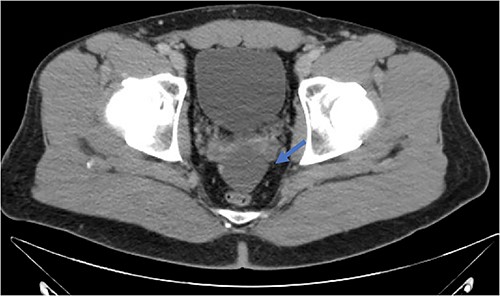

An active 41-year-old male with no significant past medical, surgical, or significant family history presented to the emergency department for evaluation of right lower quadrant abdominal discomfort that started three days prior to arrival. He did not report any associated trauma or systemic signs of disease, including fever, chills, night sweats, or weight loss. On physical exam, the patient did not appear to be in any distress and was otherwise well-appearing. He had mild right lower quadrant tenderness on palpation without rebound, guarding, or peritoneal signs. Diagnostic studies included a contrast-enhanced CT scan of the abdomen and pelvis, which revealed two fluid collections in the region of the appendix and the cul-de-sac, measuring ~21 Hounsfield units, without evidence of active inflammation (Fig. 2). His labs were otherwise unremarkable. Given these findings, he was initially treated for perforated acute appendicitis with abscess. Antibiotics were started, and the decision was made to drain the fluid collection. Diagnostic laparoscopy or drainage of the fluid collection by interventional radiology was not pursued given the risk of potentially seeding a malignant process. Since the patient continued to have persistent symptoms and the differential diagnosis included lesions with malignant potential, the decision was made to proceed with exploratory laparotomy for both diagnostic and therapeutic purposes.

Fluid collection is present in the cul-de-sac that measures 5.8 × 4.8 × 2.9 cm (blue arrow).